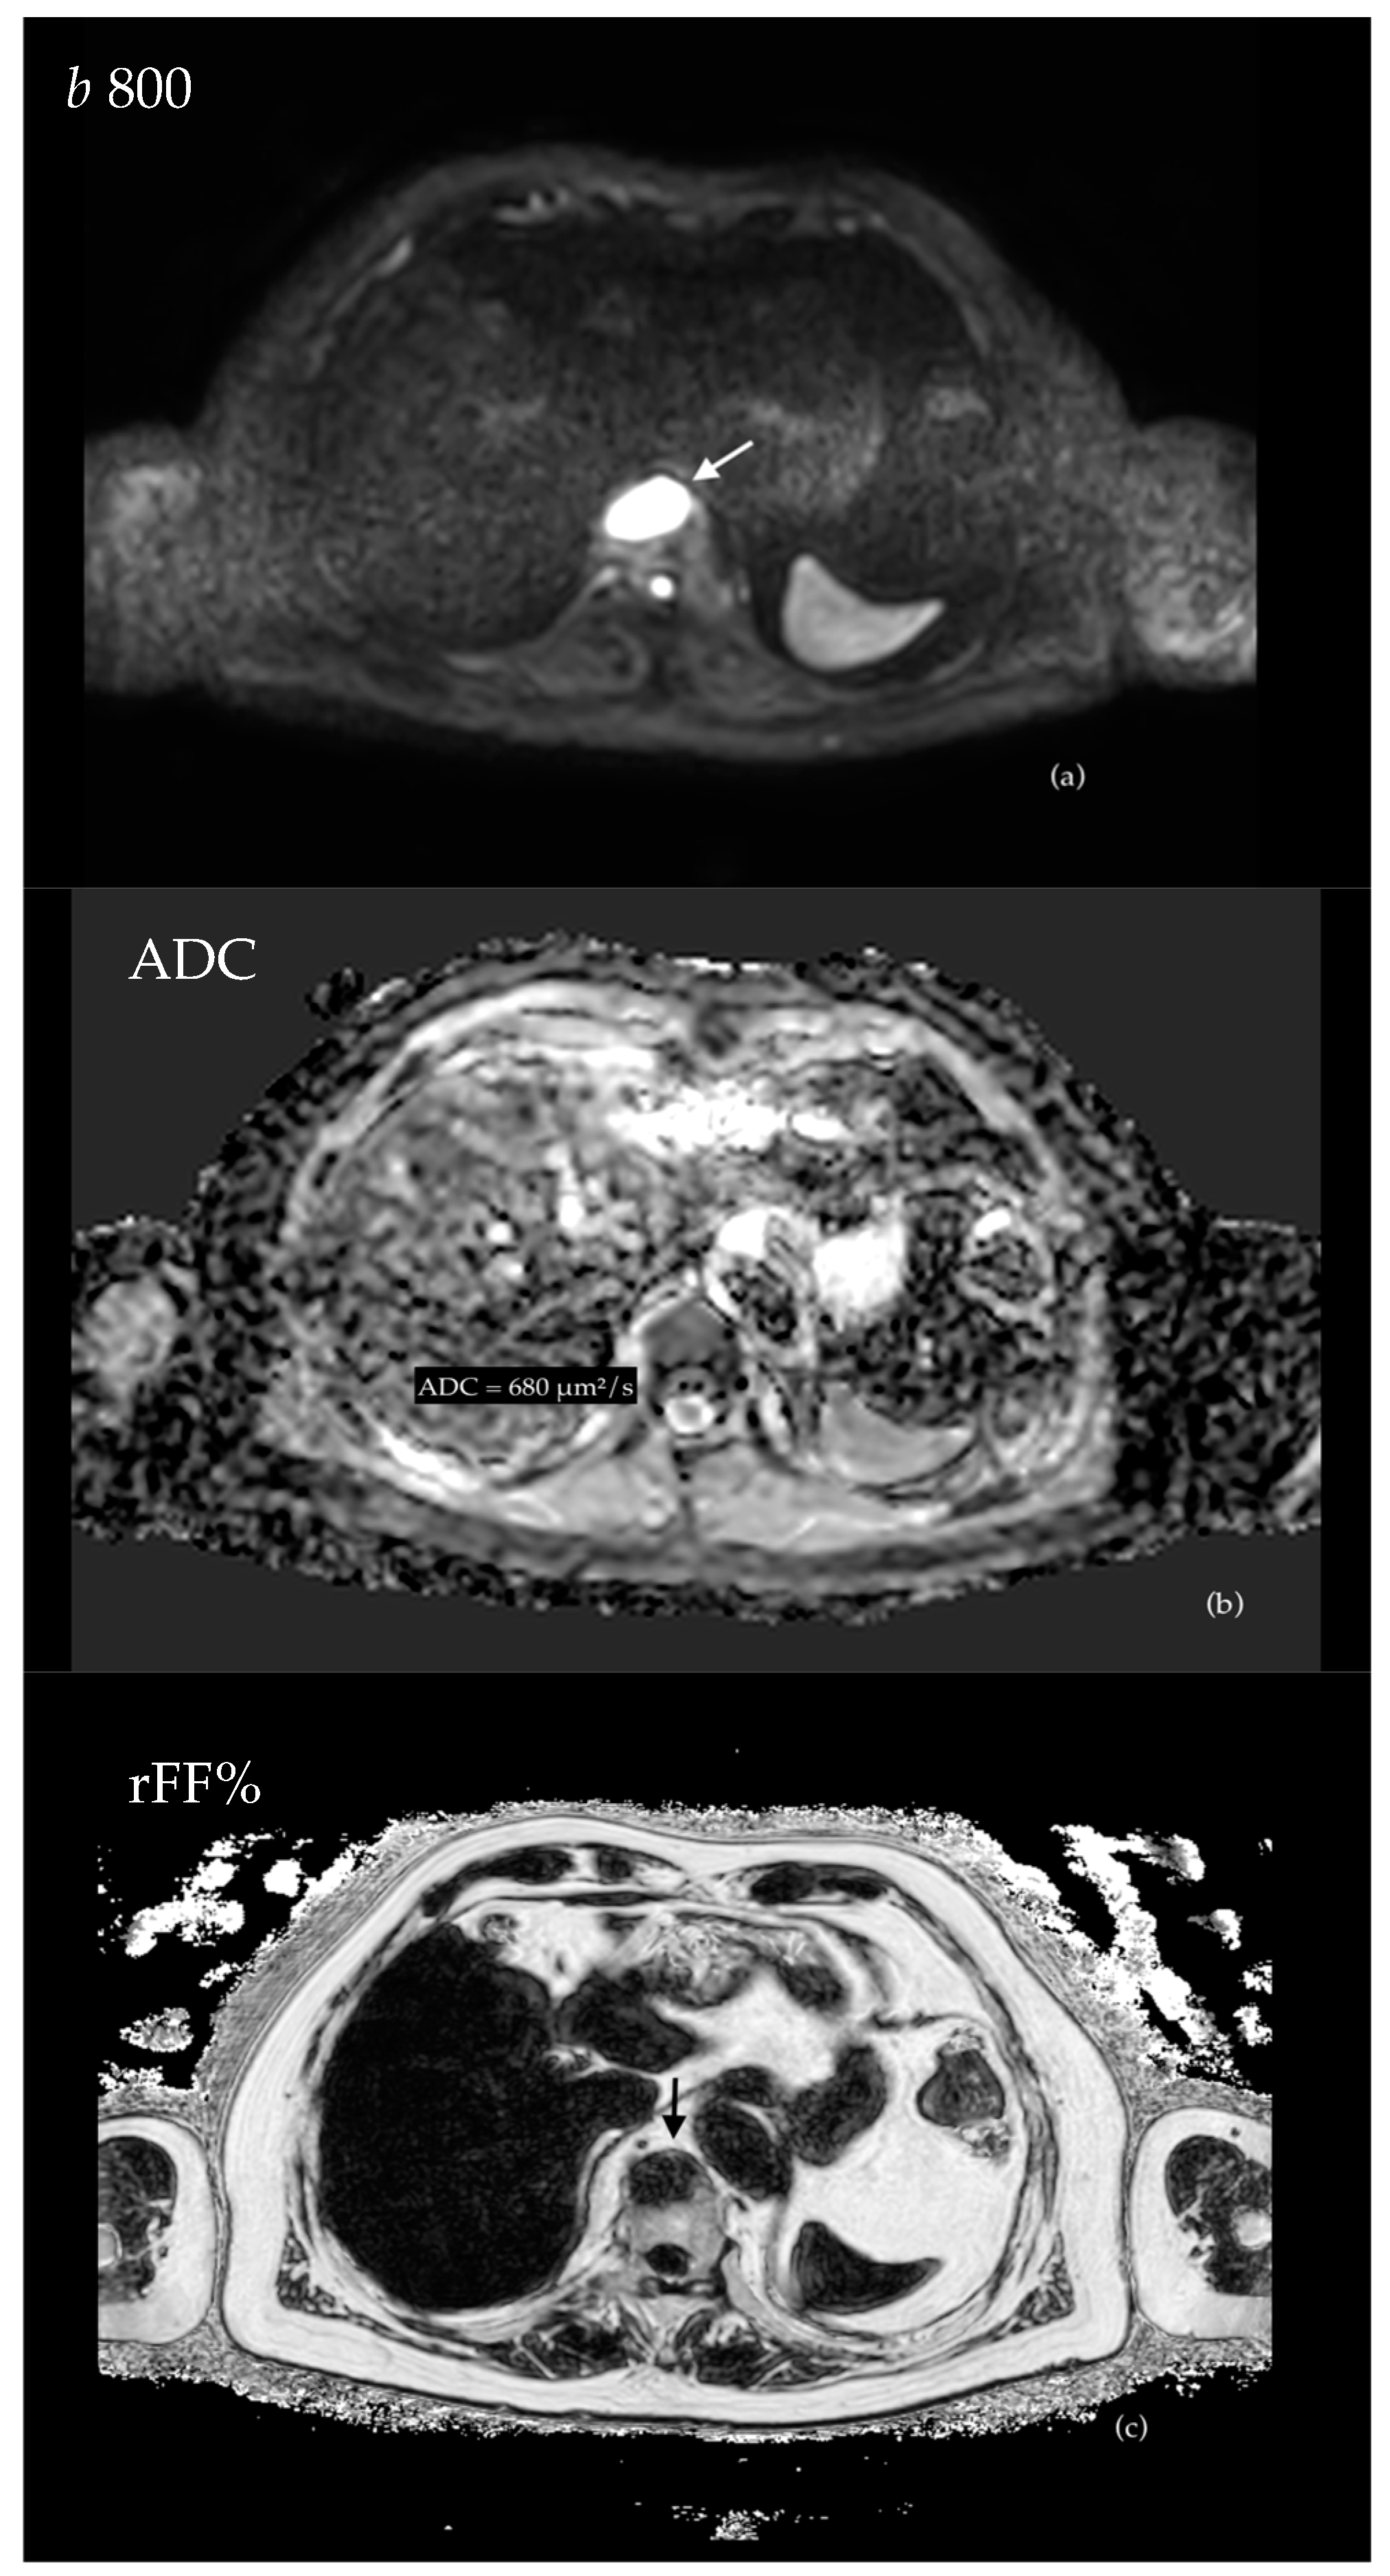

3.4.1. Evaluation of Bone Metastases with WB-MRI

- Castagnoli, F.; Donners, R.; Tunariu, N.; Messiou, C.; Koh, D.-M. Relative fat fraction of malignant bone lesions from breast cancer, prostate cancer and myeloma are significantly lower than normal bone marrow and shows excellent interobserver agreement. Br. J. Radiol. 2023, 96, 20230240. [Google Scholar] [CrossRef] [PubMed]